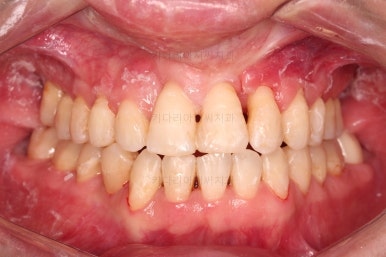

1. 초진 시 입안의 모습

부산구순구개열교정 키다리아저씨치과에 처음 내원하셨을 당시의 입안의 모습입니다.

구순구개열 환자분의 일반적인 입 안의 특징은 다음과 같습니다.

골 결손부위의 치아 결손이 빈번하다.

구개열 봉합술을 어린 나아이에 받기 때문에, 해당 부위의 상흔이 남는다.

상흔의 영향으로(피부 상처도 일반 피부 보다는 상처가 아문 부위가 더 단단하죠.) 입천장의 잇몸이 굉장히 단단하다.

그래서 가로폭의 성장이 잘 되지 못하여 악궁(치아가 배열된 U자 형태)이 협착된 경우가 많다.

공간 부족으로 치열이 매우 삐뚠 경우가 많다.

공간 부족과 악궁 형태 등으로 인해 부정교합이 함께 나타난다.

골 결손부위 근처의 치아는 뼈가 약한 경우가 많아 튼튼하지 못하고 만지면 흔들리는 경우가 많다.

이번 환자분도 이와 같은 일반적인 특징이 그대로 나타나 있었습니다.

양측성 구순구개열이었으므로 작은 앞니(대문니와 송곳니 사이)가 양쪽 다 결손이었고, 또 다른 이유로 아래 앞니도 1개 없는 상태였습니다.